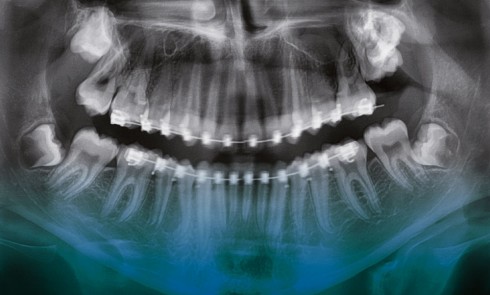

Quelles sont les indications d’extraction des dents de sagesse ? Les dents de sagesse sont les troisièmes molaires : 18, 28, 38,...Les dents de sagesse en questions

Quelles sont les indications d’extraction des dents de sagesse ? Les dents de sagesse sont les troisièmes molaires : 18, 28, 38,...